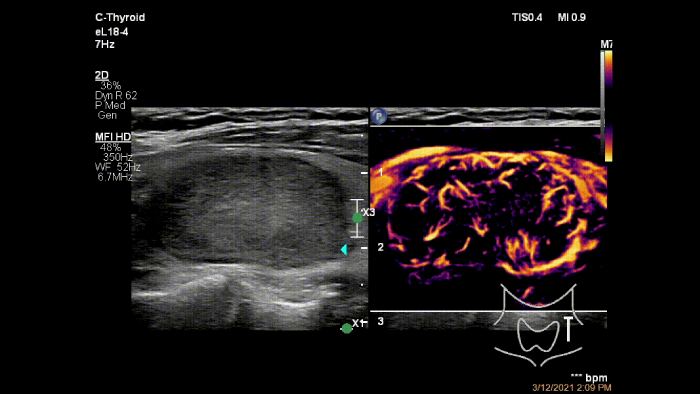

O MicroFlow Imaging ultrapassa muitas das barreiras associadas aos métodos convencionais para a deteção do fluxo sanguíneo de vasos pequenos com alta resolução e artefactos mínimos.